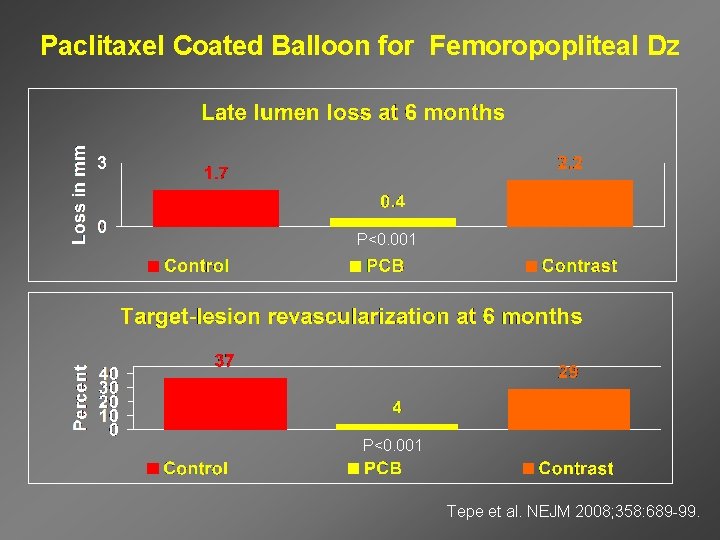

Paclitaxel Coated Balloon for Femoropopliteal Dz P<0. 001 Tepe et al. NEJM 2008; 358: 689 -99.